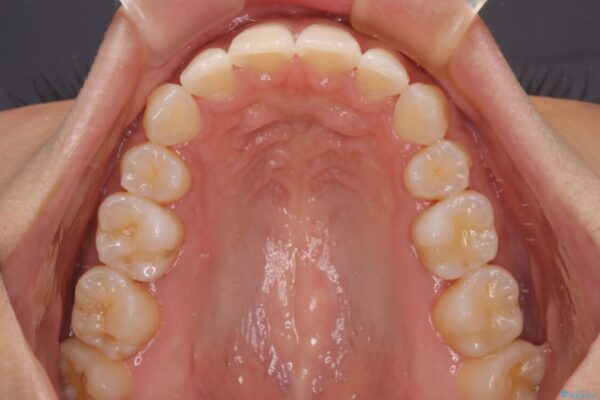

治療後

• 抜歯矯正で唇を閉じやすく 目立たないワイヤー装置 治療後画像